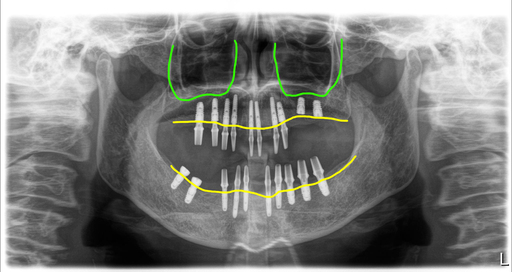

골밀도가 낮아 6개월 기다린 후 완성

상악 좌측 구치부의 상악동 윈도우 뼈이식부위 때문에 6개월 기다렸다가 치료를 마무리했어요. 그런데 이 분은 골밀도가 낮았기 때문에 만약 상악동이식이 없었다고 하더라도 6개월 정도 기다리는 방법이 더 좋았을 거라고 생각이 됩니다.

브릿지 타입으로 지르코니아에 맞춤지대주 세멘트 방식으로 치료를 했으며, 구치부는 나사구멍을 형성해서 이후 보수에 유리하도록 디자인했습니다.

그리고 치아와 치아 사이에 공간을 두어 치간치솔로 위생적으로 관리할 수 있도록 디자인했습니다.